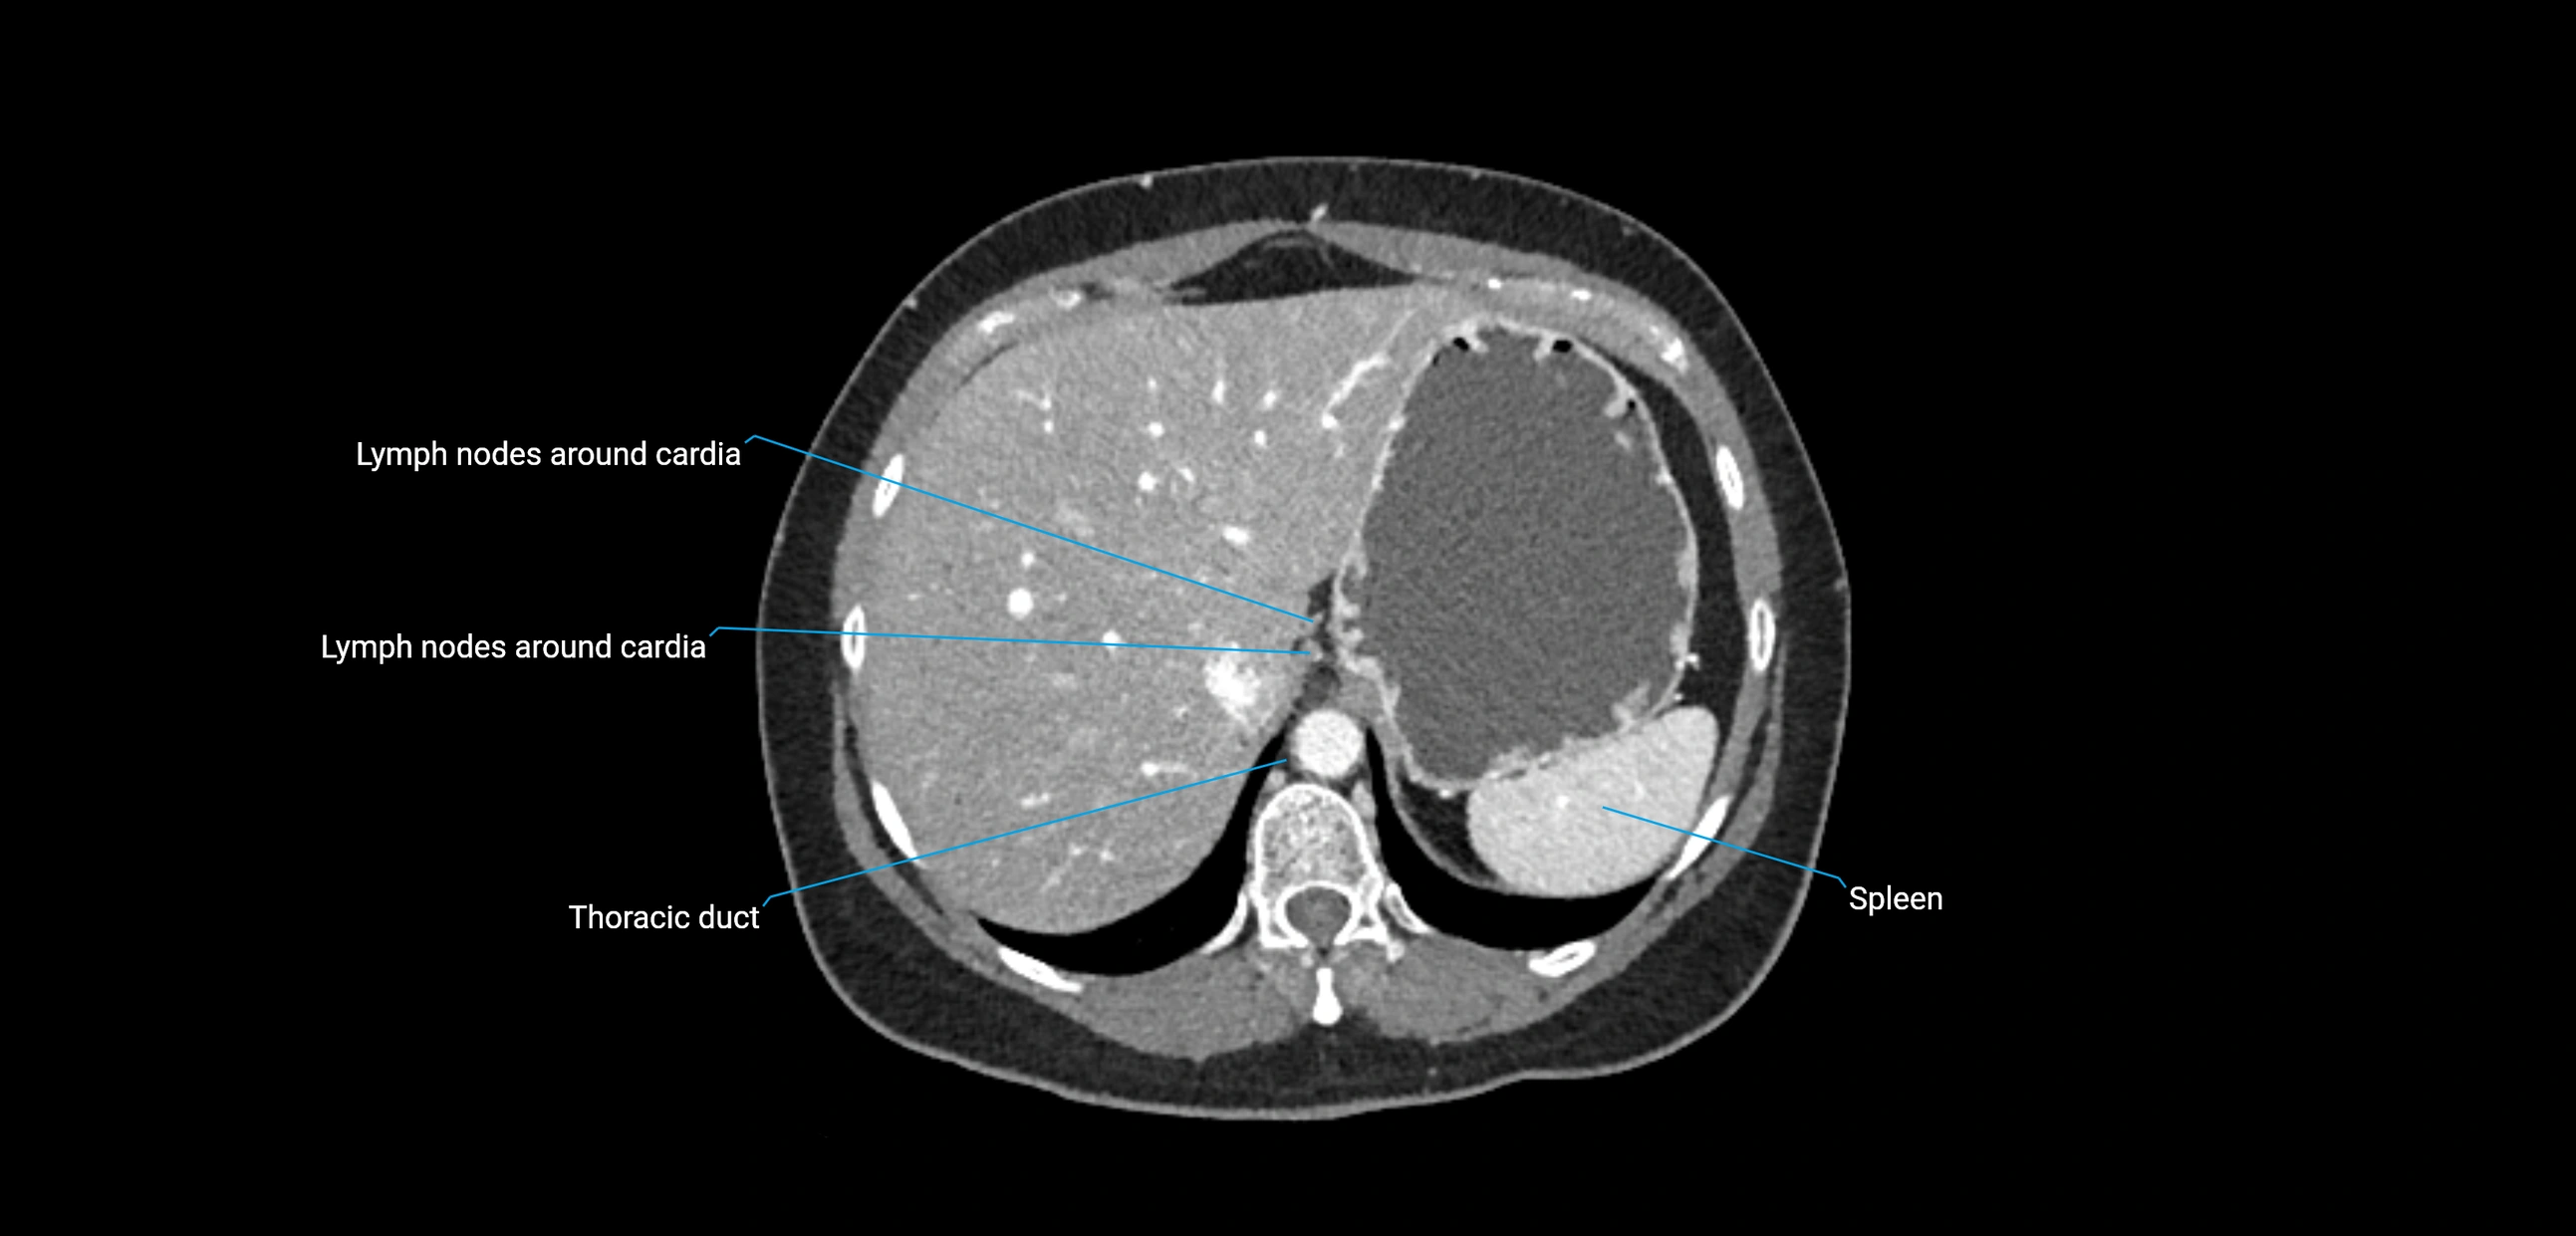

CT image

image